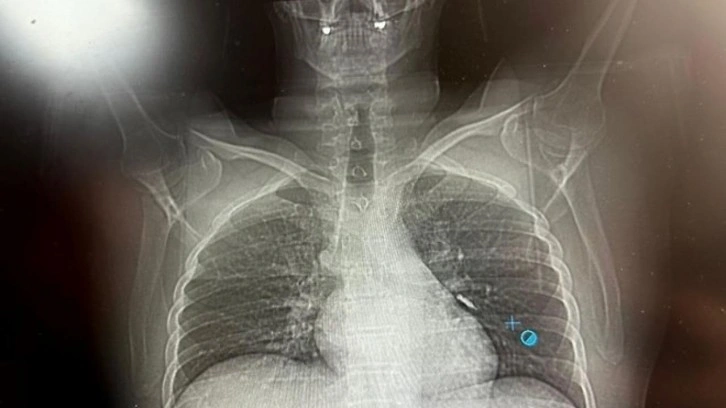

Hastaya bronkoskopi işlemi uygulandı. Sol akciğerin üst lobunda saplanmış şekilde tespit edilen vida, vidalı yapısı ve bulunduğu konum nedeniyle güçlükle yerinden oynatılabildi.

Yapılan uzun ve titiz müdahale sonrası vida yerinden çıkarılamasa da hasta bir süre sonra geçirdiği öksürükle birlikte implant vidasını midesine gönderdi. Vida, daha sonra doğal yollarla vücuttan atıldı.